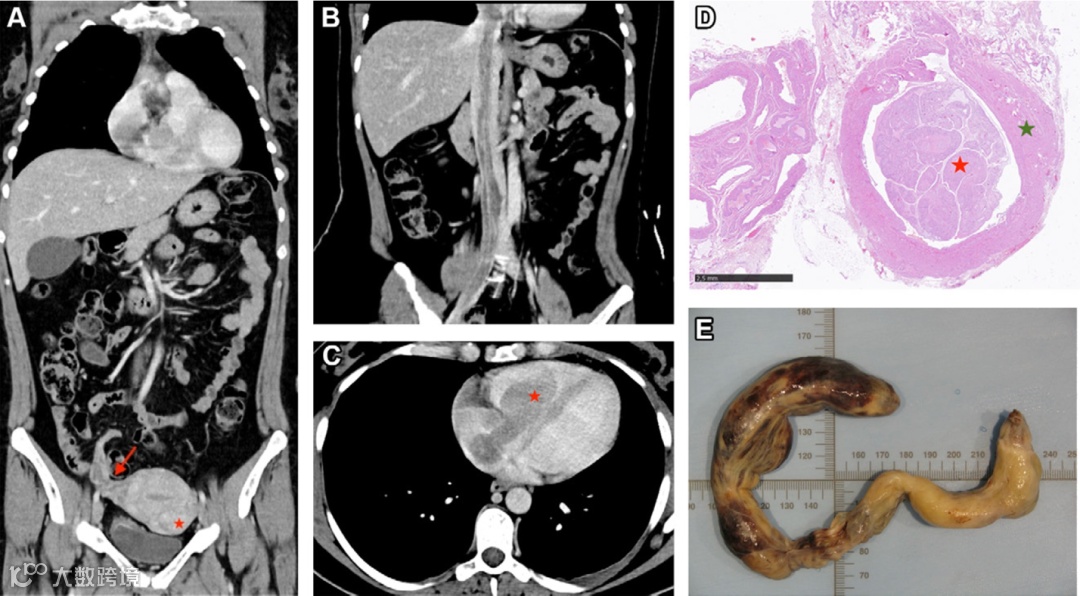

血管内平滑肌瘤病是一种少见的良性平滑肌细胞增生,可以原发形成(de novo),也可能从子宫平滑肌瘤扩展至邻近的盆腔静脉(如图1A所示),进而延伸到下腔静脉(如图1B所示)、右心腔(如图1C所示),极少情况下还可能扩展至肺血管系统。血管内平滑肌瘤病可能是由于平滑肌瘤直接扩展到邻近静脉(如图1A和图1D所示),或者由血管内膜中平滑肌的独立增殖引起的,这种疾病主要影响绝经前女性,尤其是那些有子宫平滑肌瘤或子宫切除术病史的患者。

冠状面增强静脉期CT图像(A)显示右侧子宫旁静脉丛和右卵巢静脉增大并呈异质性增强(箭头),其中可见腔内肿瘤。此外,还可见一个小的浆膜下子宫平滑肌瘤(★)。

冠状面增强静脉期曲面重建CT图像(B)显示,肿瘤从右侧髂总静脉经下腔静脉扩展至右心腔。

轴向增强静脉期CT图像(C)显示,肿瘤的心内部分位于右心房和右心室内(★)。

光学显微图(D)显示良性平滑肌瘤(红★)扩展至右卵巢静脉(绿★),肿瘤由平滑肌细胞束组成,具有丰富的血管,但无坏死或明显的有丝分裂活性。(苏木精-伊红染色,原始放大倍数×10)。

切除的血管内肿瘤标本照片(E)显示其呈长管状、类似蠕虫的外观。

这例血管内平滑肌瘤病患者的影像学表现清晰地展示了肿瘤从盆腔静脉起始并逐步扩展到右心腔的过程,同时病理学分析确认其为良性平滑肌瘤,无恶性特征。